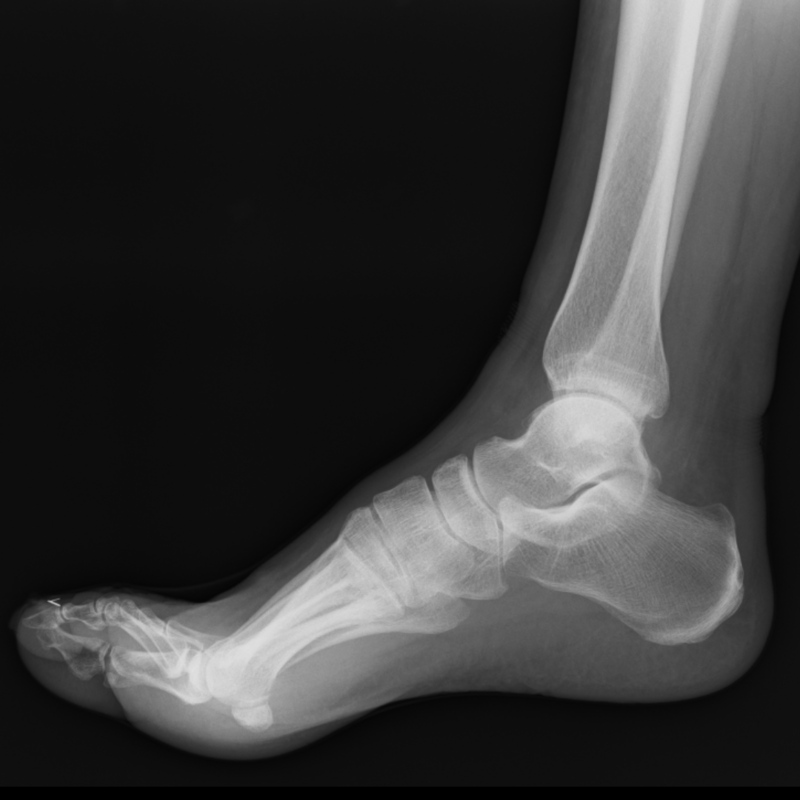

レントゲン検査

骨の形状など、画像を医師が読影します。